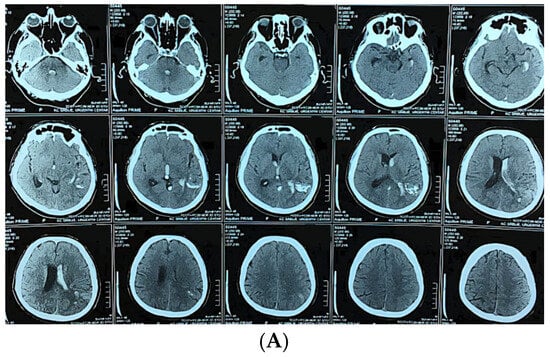

Figure 3.

A 58-year-old man presented with sudden onset of headache and vomiting. Brain CT showing initial findings of intraventricular and intracerebral hemorrhage (A). Two hours after admission he became unresponsive, GCS 6; urgent CT showed hydrocephalus (B). Brain CT after the VP shunt operation (C). CT angiography was performed, confirming the diagnosis (D). Microsurgical resection of the AVM was performed, and after the operation the patient was unresponsive with hemiplegia. Control brain CT showed cerebral infarction with intracerebral hemorrhage (E). CT after the reoperation (F) And 6 months after the operation and cranioplasty surgery (G).